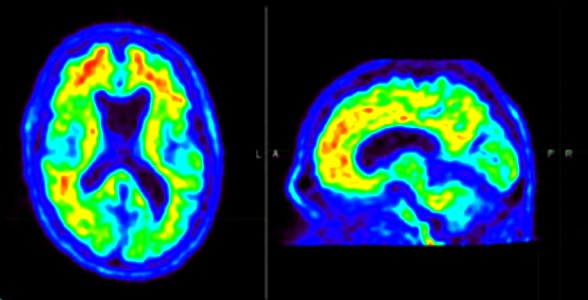

अल्जाइमर रोग (Alzheimer disease) का एक निर्धारक हॉलमार्क मस्तिष्क में एमीलॉइड बीटा पेप्टाइड्स का संचय है।

2019 में, आईआईटीगुवाहाटी के वैज्ञानिकों ने पाया कि कम-वोल्टेज, सुरक्षित विद्युत क्षेत्र के अनुप्रयोग से विषाक्त न्यूरोडीजेनेरेटिव अणुओं का निर्माण और संचय कम हो सकता है जो अल्जाइमर रोग में भूलने का कारण बनते हैं।